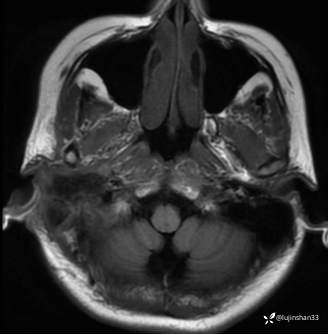

颞骨MRI: